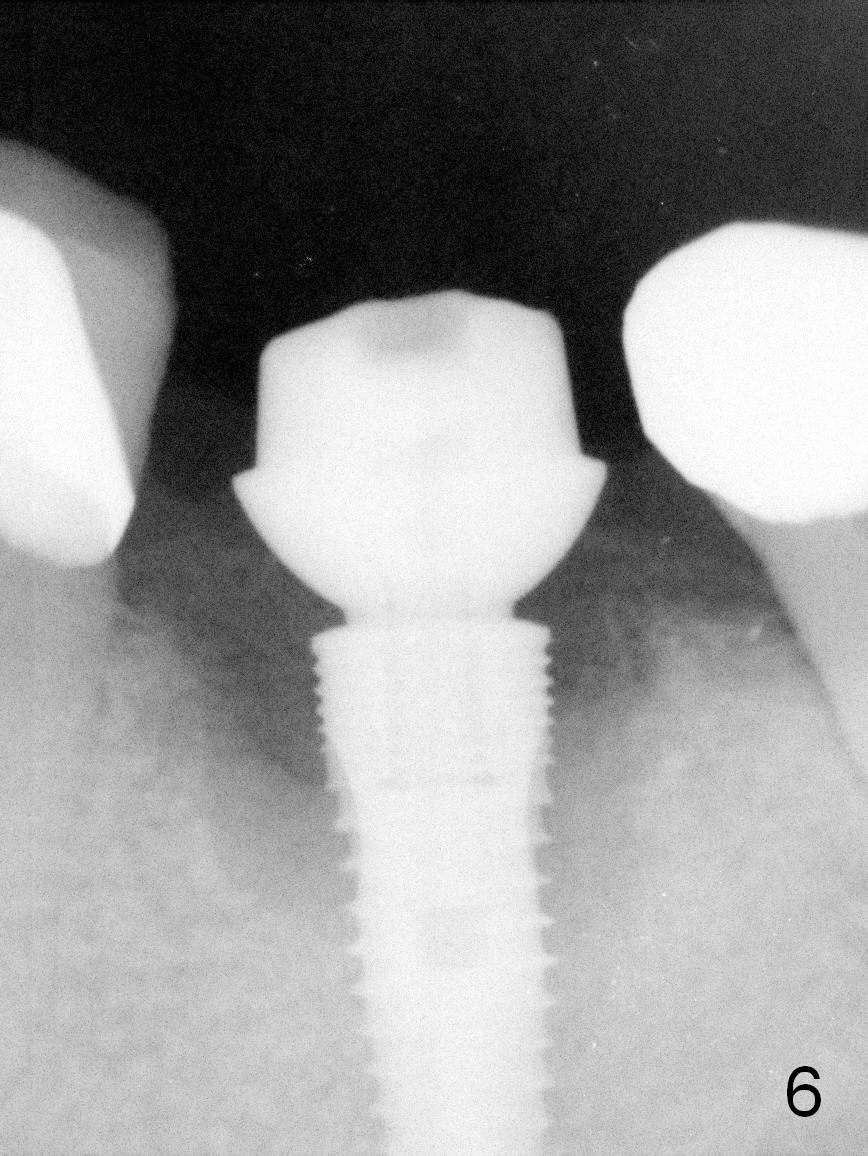

In fact, the buccal plate and the septum are defective. Osteotomy is initiated lingual to the center of the common sockets (Fig.1); depth is about 4 mm. When a 5x12 mm bone-level implant is placed (Fig.4), there is a gap mesiobuccally, which is later filled with bone graft (Fig.5 *). A large abutment (7.8x4(3) mm) is placed immediately (Fig.5 A) for an immediate provisional to close the sockets. The buccal abutment margin is ~ 1 mm subgingival, whereas the lingual ~2 mm supragingival. The abutment may need to be changed in the restorative phase (Fig.9,10).

As expected, the lingual margin of the abutment is supragingival 2 months postop. The immediate provisional is fractured (Fig.6). The abutment is changed to 5.8x4(2) mm and impression is taken.